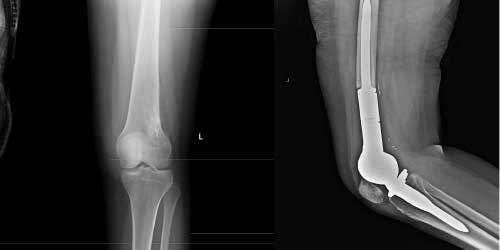

Her ameliyatın olduğu gibi kemik ve yumuşak doku tümör ameliyatlarının da riskleri vardır. Bu riskleri genel ve yapılan ameliyata özgü olmak üzere kabaca iki başlık halinde gruplandırabiliriz. Öncelikle anestezi ile ilgili risklerin anestezi uzmanı tarafından (...)

Ameliyat sonrası takip ve kontrol hastanın ameliyat masasında uyanması ile başlar. Özellikle damar ve veya siniri ilgilendiren ameliyatlarda hasta ameliyat masasından alınmadan ekstremitenin dolaşımı ve ilgili sinirin fonksiyonu kontrol edilir.